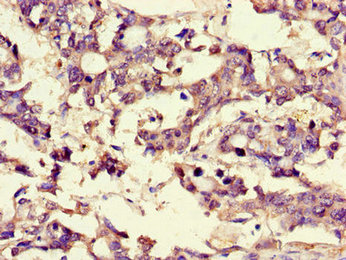

Immunohistochemistry of paraffin-embedded human liver cancer using CSB-PA002816LA01HU at dilution of 1:100